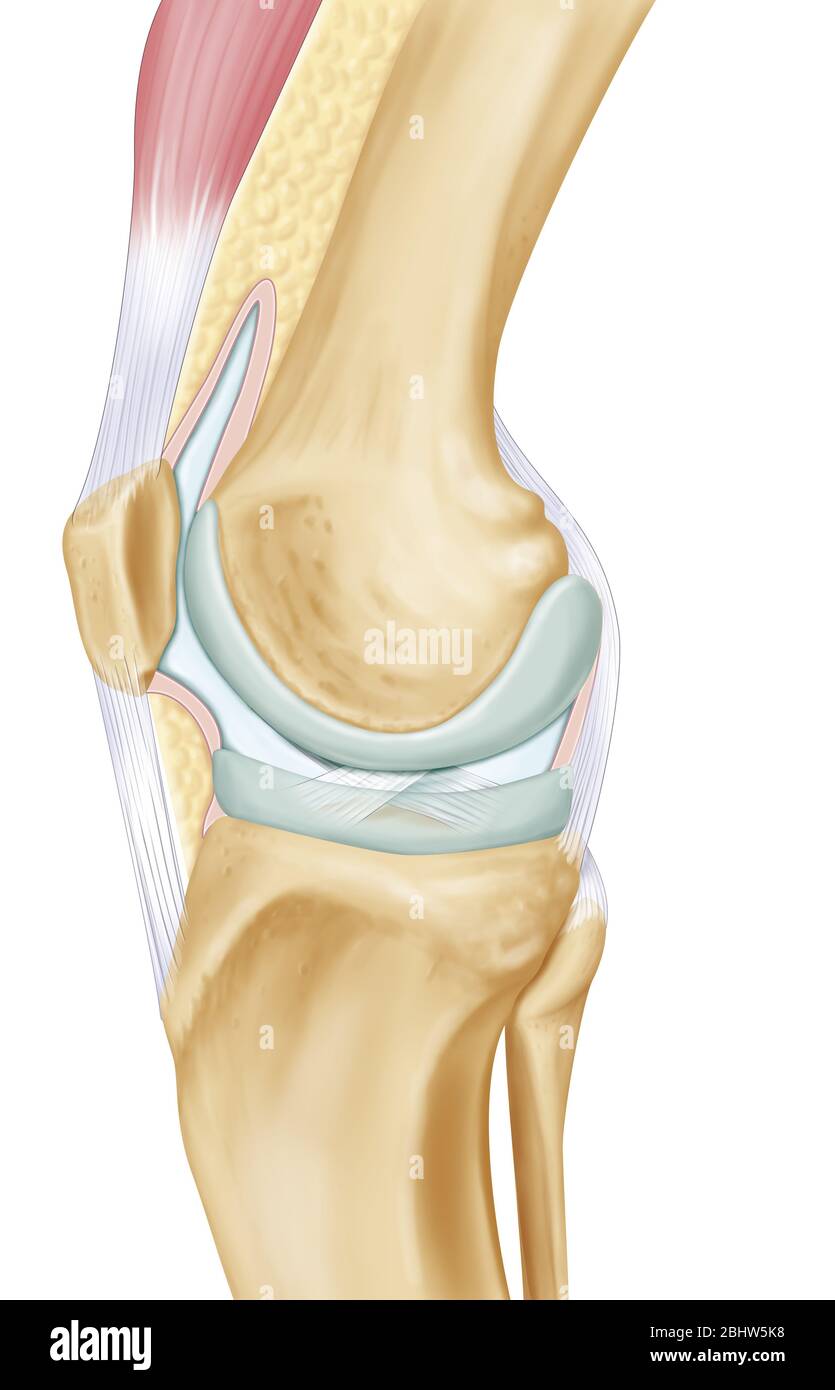

Representation of the knee joint on an internal lateral view of the right leg. At the center of the illustration are the two articular surfaces in gra Stock Photohttps://www.alamy.com/image-license-details/?v=1https://www.alamy.com/representation-of-the-knee-joint-on-an-internal-lateral-view-of-the-right-leg-at-the-center-of-the-illustration-are-the-two-articular-surfaces-in-gra-image355209772.html

Representation of the knee joint on an internal lateral view of the right leg. At the center of the illustration are the two articular surfaces in gra Stock Photohttps://www.alamy.com/image-license-details/?v=1https://www.alamy.com/representation-of-the-knee-joint-on-an-internal-lateral-view-of-the-right-leg-at-the-center-of-the-illustration-are-the-two-articular-surfaces-in-gra-image355209772.htmlRM2BHW5K8–Representation of the knee joint on an internal lateral view of the right leg. At the center of the illustration are the two articular surfaces in gra